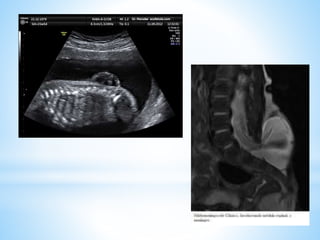

*Encefalocele

Diagnostico

Prenatal

Ecografía

Alfa-proteínas maternas

Posnatal

Parto por cesaría

TC

RM

*Mielomeningocele

* Es una anomalía del desarrollo caracterizada por la

ausencia del arco posterior vertebral y de la piel, con

exteriorización de las meninges y la medula espinal,

abiertas y malformadas.

• Diagnostico: midiendo las alfa-fectoptoteinas y

ecografía uterina.

• Se asocia: Sx de Chiari, estenosis del acueducto

d Silvio e hidromielia.